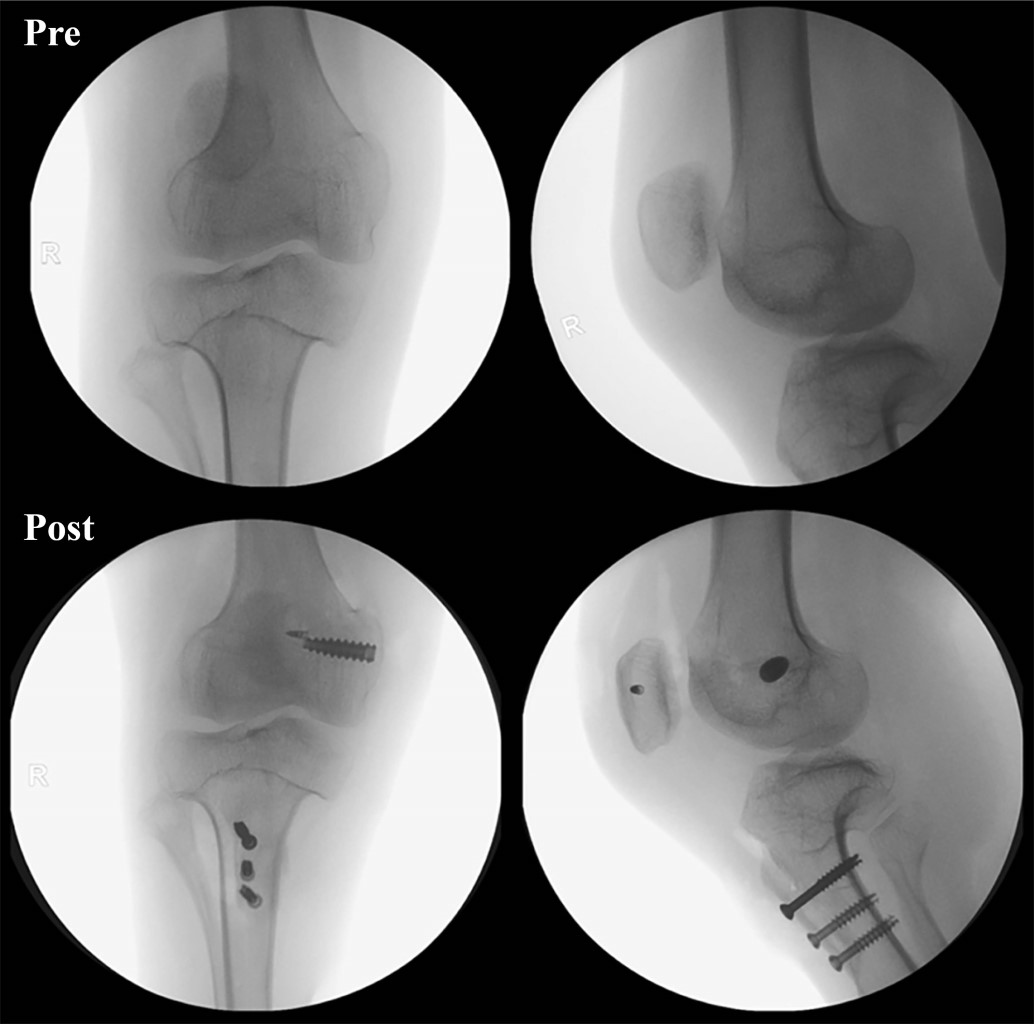

La inestabilidad patelofemoral es una condición multifactorial que abarca un espectro de manifestaciones que van desde subluxaciones hasta luxaciones completas de la rótula. Desde el punto de vista etiológico, puede originarse a partir de diversas anomalías anatómicas, incluyendo la alineación de las extremidades, la morfología ósea de la articulación patelofemoral y la integridad de los estabilizadores estáticos y dinámicos. Los pacientes con amputación por debajo de la rodilla tienen un mayor riesgo de experimentar inestabilidad patelofemoral. Este informe describe un caso que involucra a un paciente con inestabilidad patelofemoral y una amputación transtibial, tratado de manera efectiva con realineación distal y estabilización patelar lograda mediante la reconstrucción del complejo patelofemoral medial (CPFM).

Figura 4